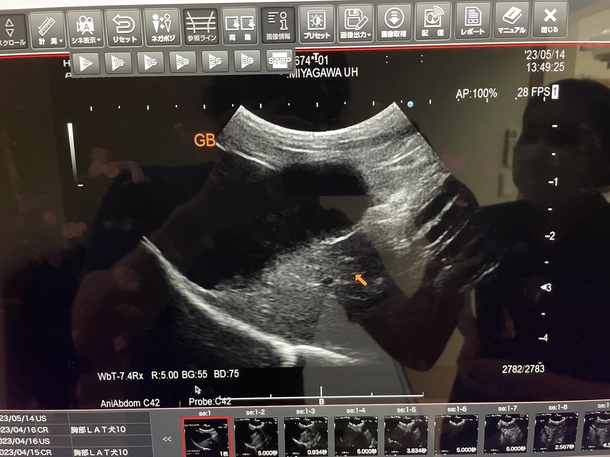

うーちゃん術前検査

うーちゃん術前検査に行って来ました。安全に手術を受けられるよう色んな所を検査します。

その結果、腎臓にとても不安な点が見つかってしまいました、、、

率直に申し上げると、心臓の手術を行うにも相当な影響を伴うレベルのようです。手術をするか否か、よく考えるべきだと病院から言われました。